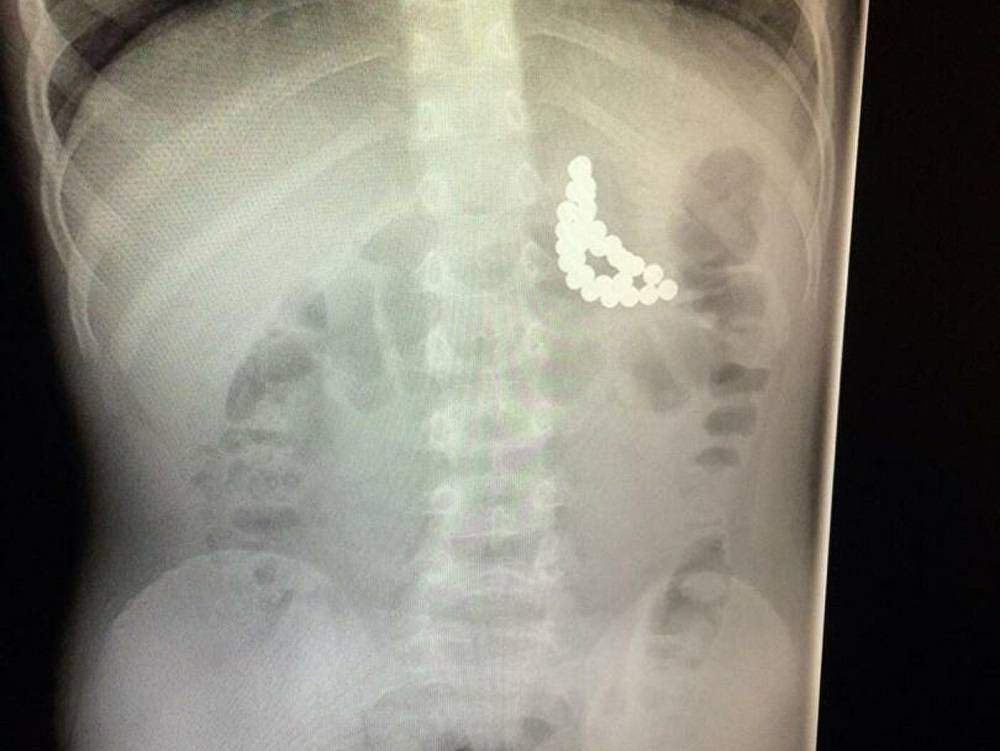

Монета в дыхательных путях

Бронхи

Если монета попала в бронхи, то ребенка также может беспокоить кашель, рвота или одышка, но симптомы будут менее выраженными, а иногда и вовсе не заметными до поры до времени. Попавшее в бронхи инородное тело опасно тем, что со временем в дыхательных путях начинается воспаление. Для извлечения монеты применяется бронхоскопия, которая делается под общим наркозом с искусственной вентиляцией легких.

Посещение врача не будет лишним, когда ребенок проглотил инородный предмет, но изменений в его поведении и самочувствии не наблюдается. Если в течение определенного времени предмет не выходит наружу самостоятельно, то врач назначает рентгенографию, чтобы детальнее узнать месторасположение монетки.